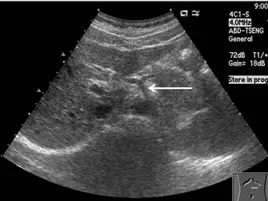

71.附圖為腹部超音波掃描影像,箭號所示的構造應為下列何者?

- 影像顯示為上腹部橫切面超音波掃描(transverse abdominal ultrasound)。

- 影像中央偏下方(解剖位置為後方)可見一個大型、圓形且具明顯管壁的無回音區(anechoic area),此為腹主動脈(abdominal aorta)。

- 從腹主動脈的前壁,有一條較粗的血管短幹向前分支出來,並隨即向左右兩側分叉,形成經典的「海鷗標誌」(seagull sign)。

- 在此海鷗標誌中,海鷗的「身體」為腹腔動脈幹(celiac trunk);海鷗的「右翼」(位於影像左側,因超音波探頭方向使影像左右相反)為總肝動脈(common hepatic artery);「左翼」(位於影像右側)為脾動脈(splenic artery)。

- 圖中白色箭號所指的位置,正是由腹主動脈向前發出、尚未分叉前的血管短幹,即為腹腔動脈幹(celiac trunk)。